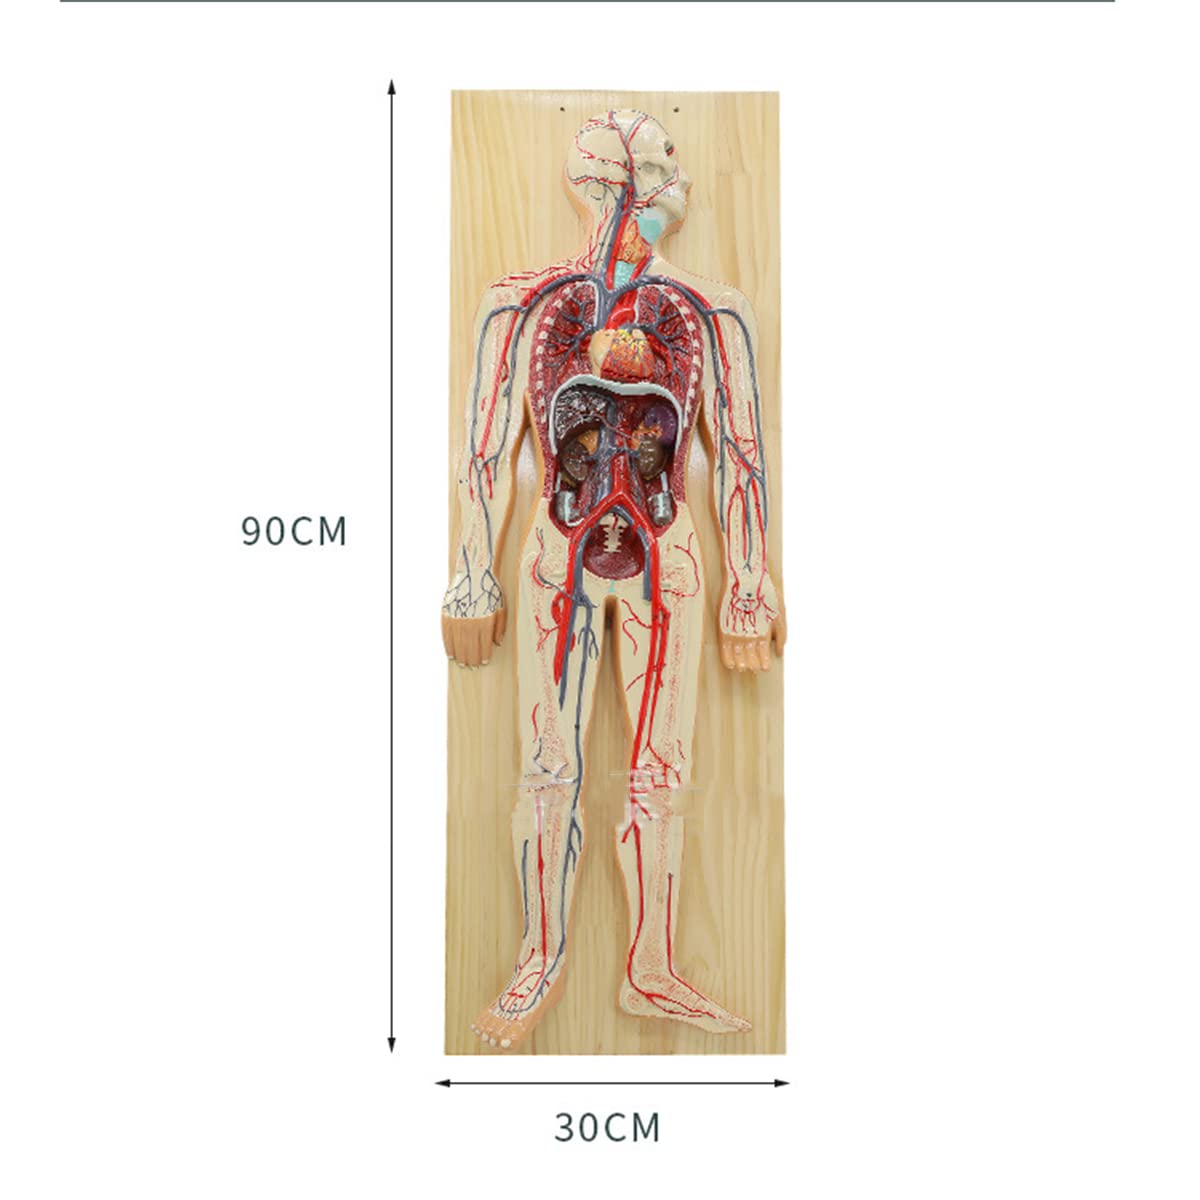

- Features: This model shows the structure of blood circulation in various parts of the human body. The circulatory system is the channel through which blood flows in the body and is divided into two parts: the cardiovascular system and the lymphatic system. Blood circulation route: superior and inferior vena cava → right atrium → right ventricle → pulmonary artery - → alveolar surrounding → pulmonary veins - >> left atrium → left ventricle → aorta - → systemic tissues (except lung). Product Size: Using this model helps to understand the composition and structure of human blood circulation. The size of the model is 1/2 the size of the human blood circulatory system. Product size: 90*30 cm/35.4*11.8 inches. High Quality: High-quality prototypes, sturdy hand-made, not fragile, made of high-quality environmentally friendly PVC, fine workmanship, creating good objects with clear shapes and rich details. Meticulous workmanship: The model has meticulous workmanship, realistic details, clear texture, easy to use and easy to observe. This product comes with a base, which is convenient for learning and teaching. Good Teaching Aids: This collection is designed for anatomy professionals and students. We are sure you will love these models. Can also be given as a gift to educators or doctors, excellent educational tool for students/teachers/professionals.

Product Specifications:Product name: Human Blood Circulatory System Model Product Type: Medical Teaching Model Product material: PVCProduct use: medicine, school, hospital, medical giftPackage list:Human Blood Circulatory System Model *1Notice:The monitor calibration is different, and the color of the object shown in the photo may be slightly different from the actual product. Please refer to the actual product.